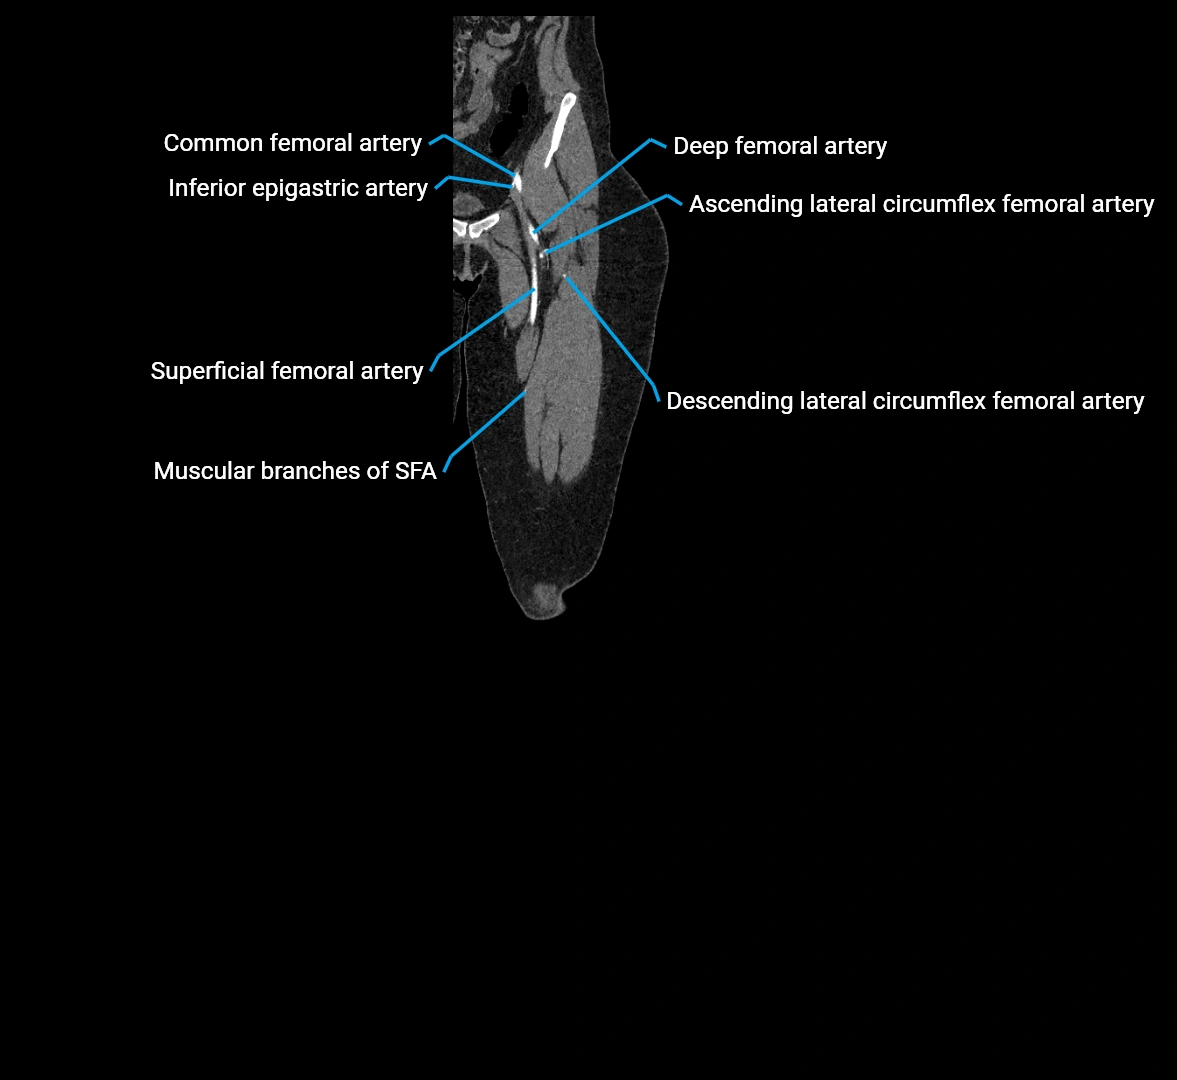

CT images

image